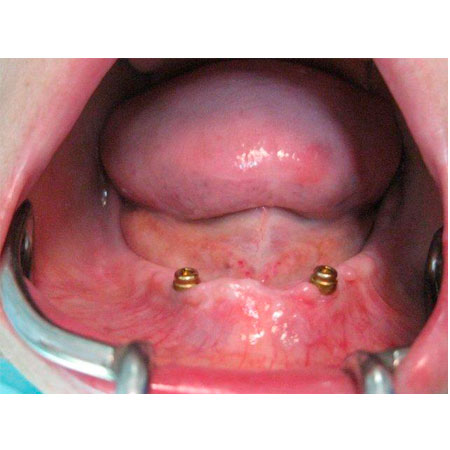

Nº3 DENTADURA COMPLETA ESTABILIZADA CON IMPLANTES

Una periodontitis muy avanzada hizo recomendable la extracción de todos los dientes y la rehabilitación de toda la dentadura mediante implantes y prótesis cerámica.